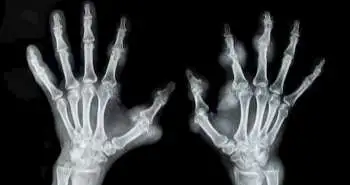

According to a recent publication of the journal, Current Rheumatology Reviews the inflammatory cytokines and oxidative stress factors among rheumatoid arthritis (RA) patients were significantly reduced using oral N-Acetyl Cysteine (NAC). As the oxidative stress and inflammation play an important role in RA pathogenesis and their suppression can stop the development of the disease. NAC is a compound which comprises both anti-inflammatory and anti-oxidant properties and therefore can be used for RA treatment.